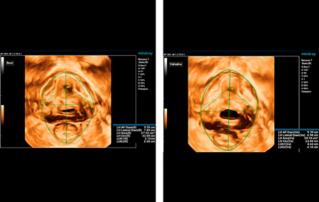

?? ?? ?? ??? ?? ?? ?? ???? ?? ???? OBG ?????? ?????. ?? ??, ?????(CNS) ??? ?? ?? ??? ?? ? ?????. ???? ?? ??? ?? ??? ??? ??? ?? MSP? 2D ????? ?? ???? ?????. ??? ?? ?? ? ??? ??? ???? ?? ???? ? ????.